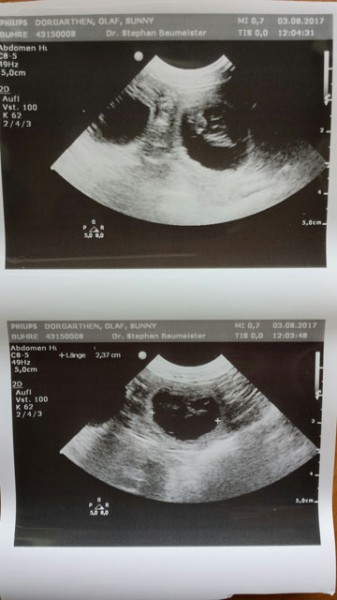

Heute war ich mit Sunny beim Ultraschall und ja...es gibt Welpen....hurraaaa!!!

• Sunny Ultraschall 03.08.2017